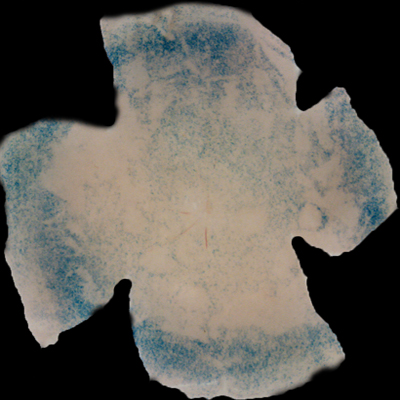

| Insulin affects cone survival in Retinitis Pigmentosa. Shown is a retinal flat mount of an rd1 mutant showing surviving cones at 7 weeks of age in blue (left panel). The rd1 mutant is part of the Retinitis Pigmentosa family of RD diseases. Rollover image to see normal cone distribution at 3 weeks of age in the same mutant before the onset of cone death. To the right is an image of a retinal flat mount at 7 weeks of age of an rd1 mutant treated for 4 weeks with daily injections of insulin showing an increased number of surviving cones. Rollover image to see what happens when endogenous insulin is removed for the same period of time. | |

Our recent studies on Retinitis Pigementosa have led us to propose that cone death is preceded by metabolic changes in cone photoreceptors and that cones die due to nutrient deprivation, in particular glucose. This hypothesis was based on gene expression changes seen at the onset of cone death in many gene that are involved in cell metabolism in addition to gene expression changes in genes that belong to the Insulin/mTOR signaling pathway. This signaling pathway is a key pathway in regulating cellular metabolism. As a proof of concept we injected mice systemically with insulin for a period of 4 weeks to test if stimulation of the pathway could improve cone survival (Figure to the right). The positive outcome of our insulin treatment reinforced our hypothesis. However, contrary to the regular action of insulin in muscle, liver and adipose tissue, where it enhances glucose uptake from the blood by release of the glucose transporter 4 to the cell membrane, the action of insulin on the retina improved glucose metabolism by changing the expression of various glycolytic genes that are regulated by the insulin/mTOR pathway.